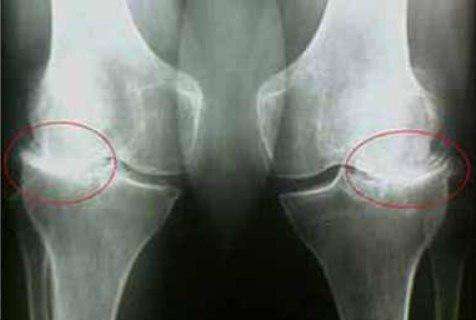

35-η

μέρα:έκανα εξετάσεις και ακτινογραφία του ώμου και του αγκώνα. Δεν υπάρχουν ίχνη αρθρώσεων! Ο

χόνδρος στις αρθρώσεις είναι σαν ενός νεαρού 30 ετών. Ο γιατρός είπε ότι στην προηγούμενη ακτινογραφία

υπήρχε πιθανότατα ένα ελάττωμα, οπότε η διάγνωση της οστεοαρθρίτιδας ήταν εσφαλμένη.

διαφορά:

πόδι μου. Ο πατέρας μου μου έφερε από κάπου το και ArtiZynt Δόξα το Θεό! Δείτε την διαφορά:

Εμένα το ArtiZynt με βοήθησε πολύ! Πρήστηκε το γόνατο δεν μπορούσα να λυγίσω το πόδι μου. Ο πατέρας μου μου έφερε από κάπου το και ArtiZynt Δόξα το Θεό! Δείτε την διαφορά: